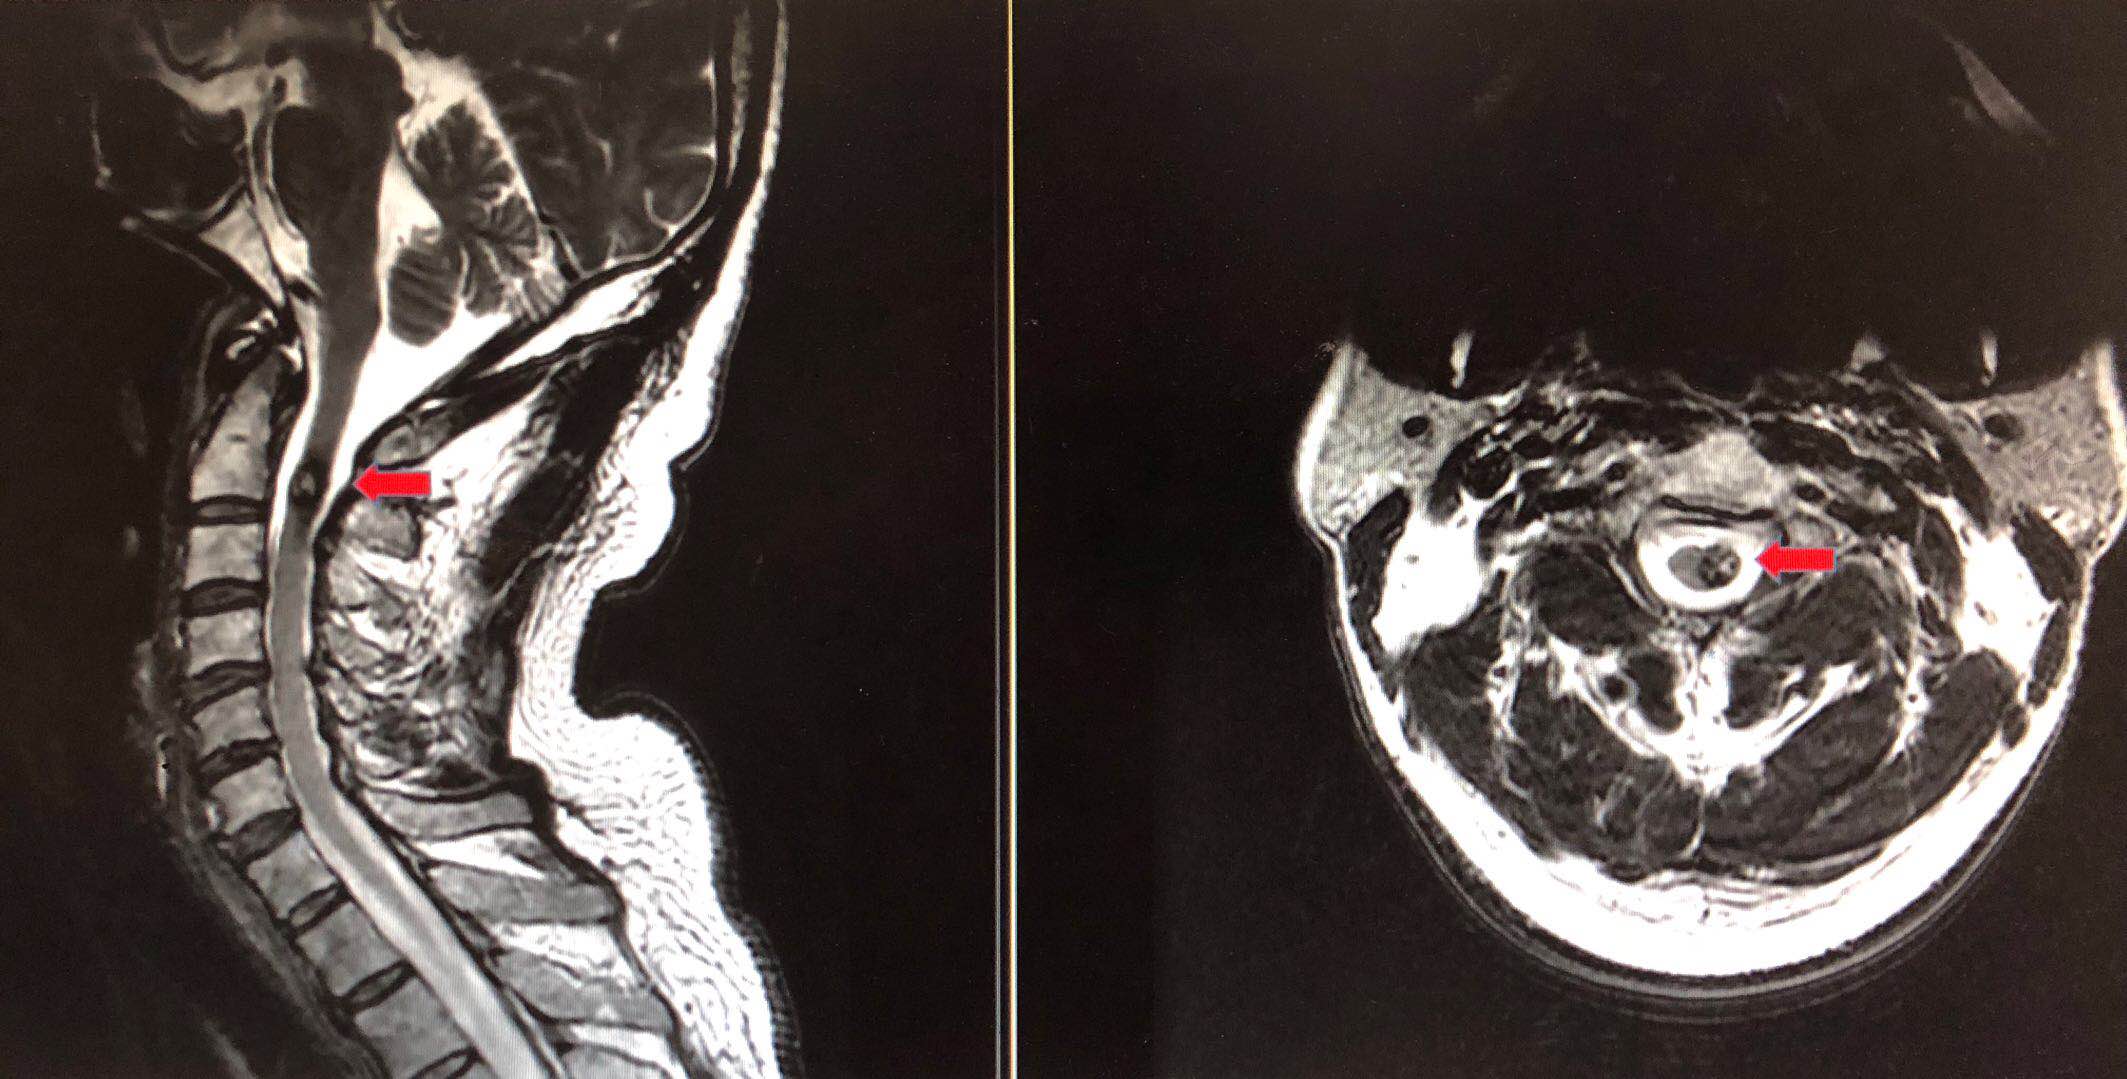

徐先生术前MRI影像,红色箭头所指为血管瘤

徐先生采取了观察和定期随访的方式,每两年做一次磁共振成像(MRI)。但2017年11月之后,他感到症状发展的速度明显加快,整个后背放射性疼痛,左手臂也开始麻木、间歇性地抽搐,而且间隔时间越来越短。医生提醒徐先生,他的血管瘤有破裂的风险,一旦破裂,可能引发大出血甚至休克。“我每天都提心吊胆,生怕出事。”徐先生的妻子说。血管瘤像是随时可能破坏他们生活的定时炸弹,面对越来越严重的症状,两人终于下定决心,进行手术治疗。